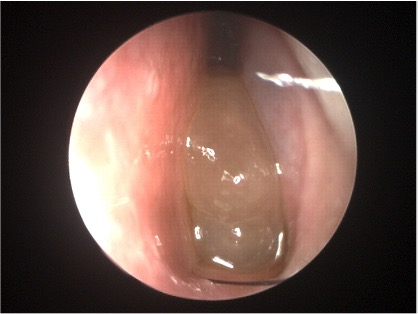

Chirurgia rinosinusale e Dupilumab a confronto nel trattamento della CRSwNP. Due studi italiani hanno messo a confronto ESS e Dupilumab nel trattamento della Rinosinusite cronica con polipi (CRSwNP).

Sono risultati entrambi efficaci nel ridurre il fattore infiammatorio responsabile della formazione dei polipi.

Dupilumab appare più indicato per pazienti anziani con controindicazioni anestesiologiche e/o pregresse chirurgie ripetute, mentre ESS rappresenta tutt’ora la prima scelta nei pazienti ancora non trattati.

Tuttavia I pazienti trattati con il farmaco biologico mostravano un maggiore miglioramento nello score dei questionari SNOT-22, VAS rhinorrhoea, VAS smell e SSIT scores, con minor ricorso alla terapia corticosteroidea orale.